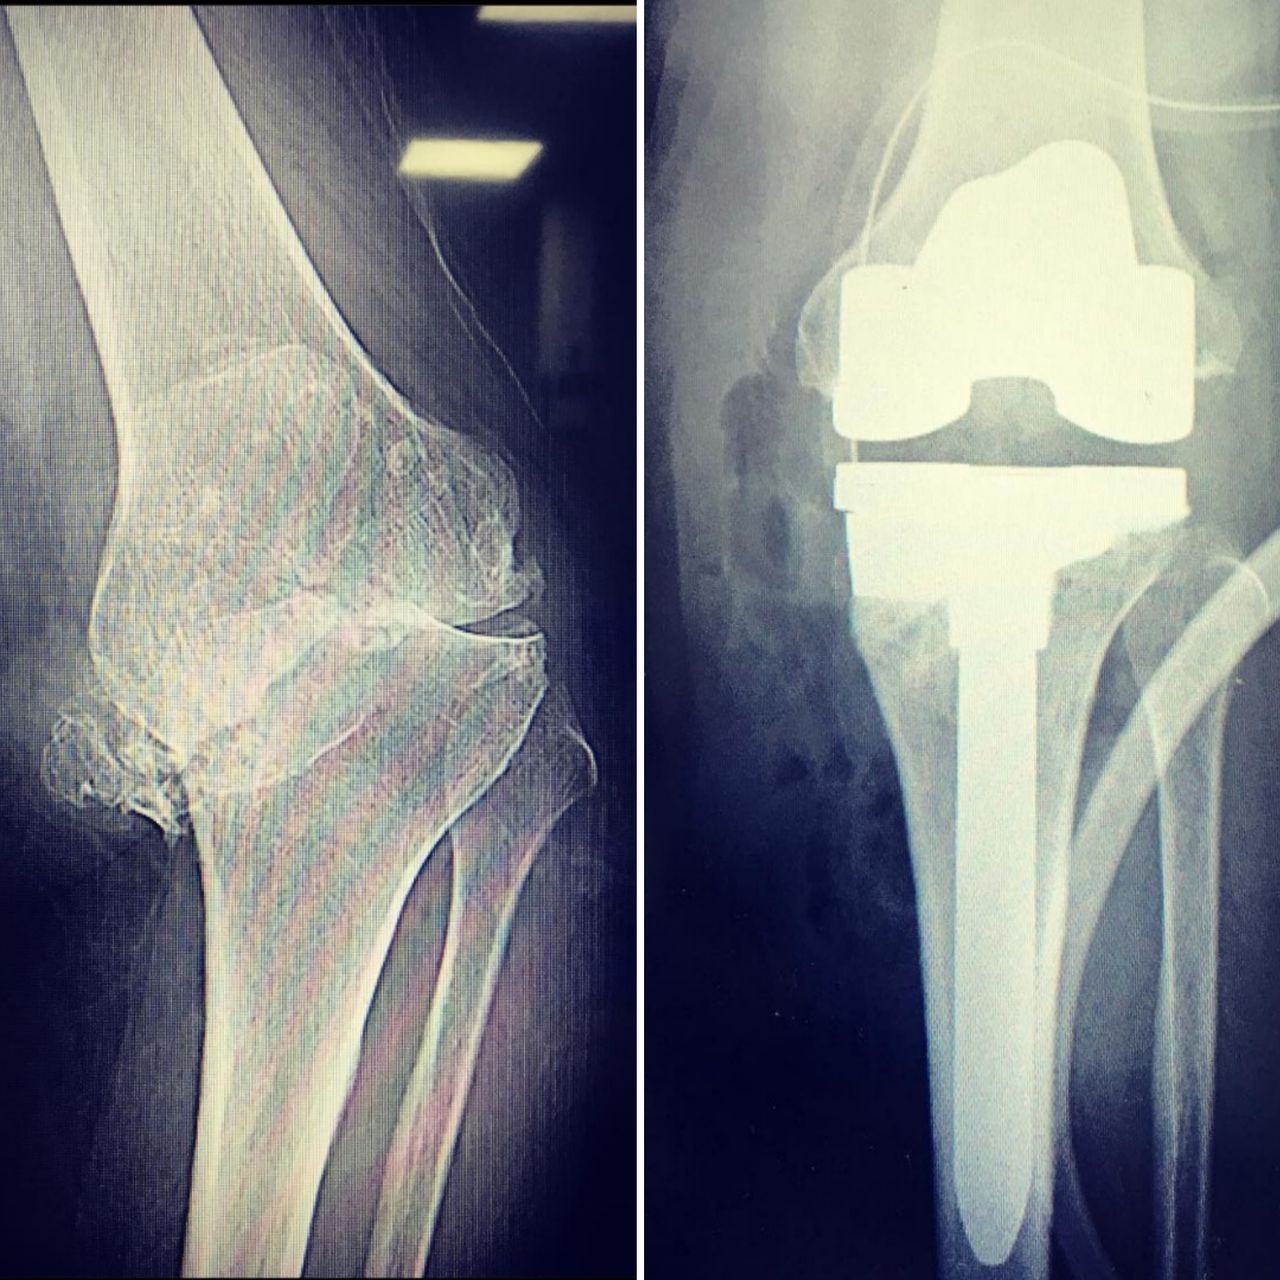

2. ALTA ESPECIALIDAD EN REEMPLAZOS ARTICULARES (PROTESIS DE CADERA, RODILLA Y HOMBRO)

• Prótesis de rodilla